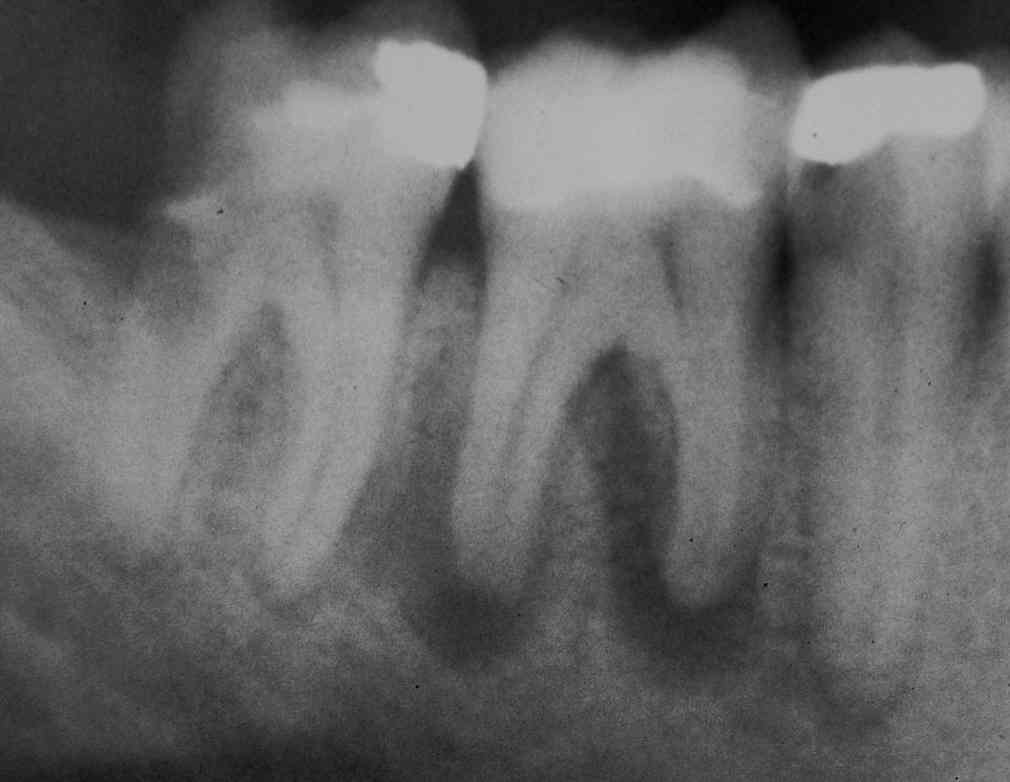

Der untere Fall zeigt darüber hinaus, dass es nicht von Nachteil ist, bei kombiniert zahn- und implantatgetragenem Zahnersatz vor dem definitiven Zementieren eine Röntgenaufnahme zu machen, um sicher zu stellen, dass man überall "ganz unten" ist. Beide Fälle zeigen, wie sicher voraussagbare Ergebnisse die genau so sorgfältige wie geduldige Desinfektion mit einem potenten Desinfektionsmittel bei der Behandlung der komplizierten Endodontitis liefert. Im oberen Fall heilen die apikalen Aufhellungen an 3 nebeneinander liegenden Zähnen synchron ab, und man hätte bei Zeitnot mit akzeptablem Risiko gleichzeitig  wurzelfüllen und überkronen, im unteren Paro-Endo-Fall gleichzeitig hemisezieren, wurzelfüllen und implantieren können..